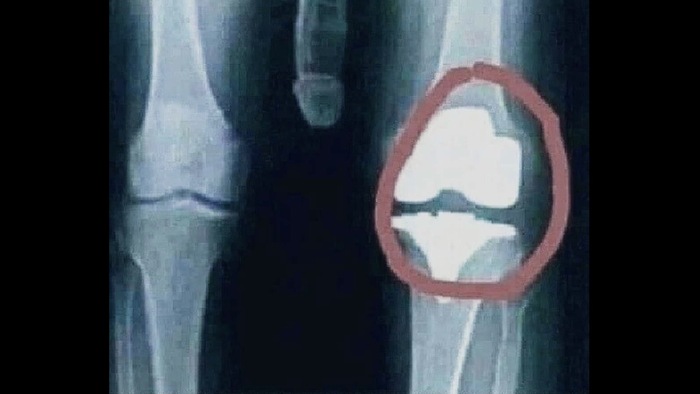

Буквально за пару часов до нашего приезда на судно чувак раскрошил себе колено. Как это было:

Экипаж уже сидел на чемоданах (концентрации ноль) и нужно было на на одной из палуб закрыть выдвижную (дополнительную) палубу. Там есть пины специальные, что-то вроде дополнительной страховки, чтобы не рухнуло в случае чего. Один пин не закрылся и надо было закрыть его руками, но так так это довольно высоко мужики взяли погрузчик, на вилки, вместо специальной клетки, насадили палет и один из матросов на него залез. Подняли его наверх, он поправил пин, но не справился с земным притяжением. Приземлился на колено и укатил под звуки сирен в госпиталь. Пережил несколько операций, но если я правильно понимаю, хоть и не врач, то вряд-ли когда-то полностью восстановится. Могу и ошибаться. Вот так и происходит, когда "хуйня, и так сойдёт" побеждает технику безопасности.

Вот рентген его колена, но это не точно